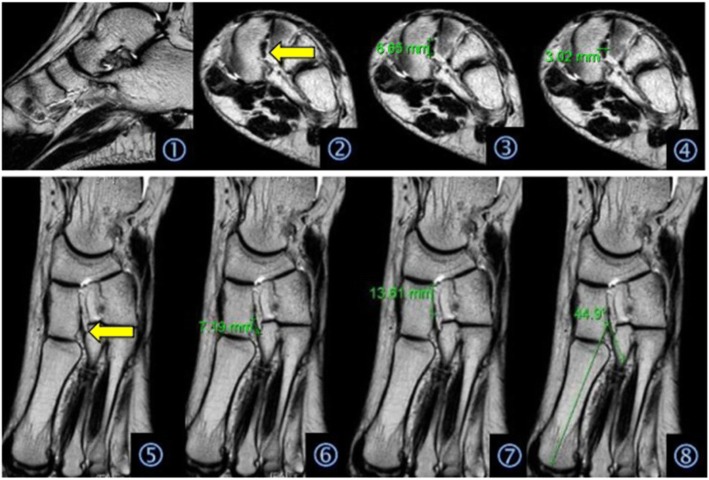

On the MRI images, the sagittal section can clearly display the corresponding situation of the Lisfranc joint bone and longitudinal arch of the foot, tolerably display the Lisfranc joint dorsal ligaments and metatarsal ligaments, and poorly display the Lisfranc ligament. The oblique coronal section can clearly display the transverse arch of the foot and clearly display the cross-section of the Lisfranc ligament. The oblique cross-section can clearly display the horizontal arch of the Lisfranc joint and more clearly display its surrounding ligaments and tendons, especially the entire Lisfranc ligament and its attachment points (Fig. 1).

Fig. 1.

Graphic interpretations: (1) MRI scanning images of the sagittal section; (2) MRI scanning images of the oblique transverse section, where the arrow indicates the Lisfranc ligament; (3) height measurement of the Lisfranc ligament; (4) width measurement of the Lisfranc ligament; (5) MRI images of the oblique coronal section, where the arrow indicates the Lisfranc ligament; (6) length of the measurement of the Lisfranc ligament; (7) measurement of the distance between the origin of the Lisfranc ligament and the base of the medial cuneiform bone; and (8) measurement of the included angle between the Lisfranc ligament and the long axis of the first metatarsal bone